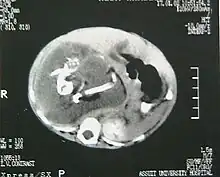

Fetus in fetu (or foetus in foetu) is a rare developmental abnormality in which a mass of tissue resembling a fetus forms inside the body of its twin. An early example of the phenomenon was described in 1808 by George William Young.[1]

A fetus in fetu can be considered alive, but only in the sense that its component tissues have not yet died or been eliminated. Thus, the life of a fetus in fetu is akin to that of a tumor in that its cells remain viable by way of normal metabolic activity. However, without the gestational conditions in utero with the amnion and placenta, a fetus in fetu can develop into, at best, an especially well differentiated teratoma; or, at worst, a high-grade metastatic teratocarcinoma. In terms of physical maturation, its organs have a working blood supply from the host, but all cases of fetus in fetu present critical defects, such as no functional brain, heart, lungs, gastrointestinal tract, or urinary tract. Accordingly, while a fetus in fetu can share select morphological features with a normal fetus, it has no prospect of any life outside of the host twin. Moreover, it poses clear threats to the life of the host twin on whom its own life depends.[4]

Fetus in fetu may be a parasitic twin fetus growing within its host twin. Very early in a monozygotic twin pregnancy, in which both fetuses share a common placenta, one fetus wraps around and envelops the other. The enveloped twin becomes a parasite, in that its survival depends on the survival of the host twin, by drawing on the host twin's blood supply. The parasitic twin is anencephalic (without a brain) and lacks some internal organs, and as such is unable to survive on its own. As the host twin has to "feed" the enveloped twin from the nutrients received over a single umbilical cord, they usually die before birth.